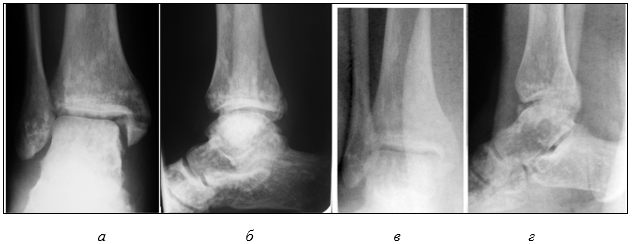

Госпитализирован в травматологическое отделение в экстренном порядке. На рентгенограмме костей, образующих голеностопный сустав травмированной ноги, выявлено наличие очагов склероза, в связи с чем решено было сделать сравнительную рентгенограмму правого голеностопного сустава. В заключении рентгенолога добавлено в описании: «…также определяются очаги остеосклероза размерами от 0,3х0,3см до 0,8х0,9см с ровными чистыми контурами». Сопутствующий рентгенологический диагноз: «Фиброзная дисплазия» (рис. 2 а, б). Диагноз «фиброзная дисплазия» после проведения консилиума по рентгенограммам более опытными рентгенологами заменен на диагноз «остеопойкилия».

Учитывая то, что стояние после репозиции внутренней лодыжки было неудовлетворительным, после спадения отека, через 10 дней произведена операция: «Открытая репозиция наружной лодыжки, остеосинтез пластинкой, внутренняя лодыжка синтезирована винтом и деротационными спицами. Остеосинтез дистального межберцового синдесмоза позиционными винтами» (рис. 2 в, г).

Рис. 2 (архив автора). Пациент Г., 25 лет. Сравнительная рентгенограмма правого (а, б) и левого (после операции) голеностопного сустава (в, г)

Окончательный диагноз при выписке: «Закрытый перелом внутренней лодыжки, краевой перелом заднего края большеберцовой кости, разрыв дистального межберцового синдесмоза, подвывих стопы кнаружи. Остеопойкилия дистального эпиметафиза обеих большеберцовых, малоберцовых костей и костей корня стопы (таранной, пяточной, кубовидной, ладьевидной и клиновидной костей обеих стоп)».

Сращение перелома произошло в обычные сроки. Динамизация межберцового синдесмоза произведена через два месяца со дня операции. Через три месяца иммобилизация прекращена. Рекомендовано удалить металлические конструкции через 8-12 месяцев. На контрольный осмотр пациент не явился.